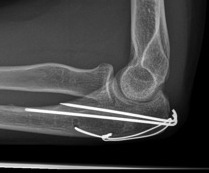

Tension band wire

Indication

Fracture proximal to center of rotation / midpoint of trochlea

Convert tensile distraction force of triceps into a compressive force

Issue

High rate of metal prominence / need for removal

Contra-indication

Fracture distal to center of rotation

Highly comminuted fractures

Oblique fractures

Technique

- fix with unicortical K wires

- drill hole in ulna distally

- pass 20 gauge wire and form figure of 8 wire about wires, can pass under triceps

- twist via 2 knots